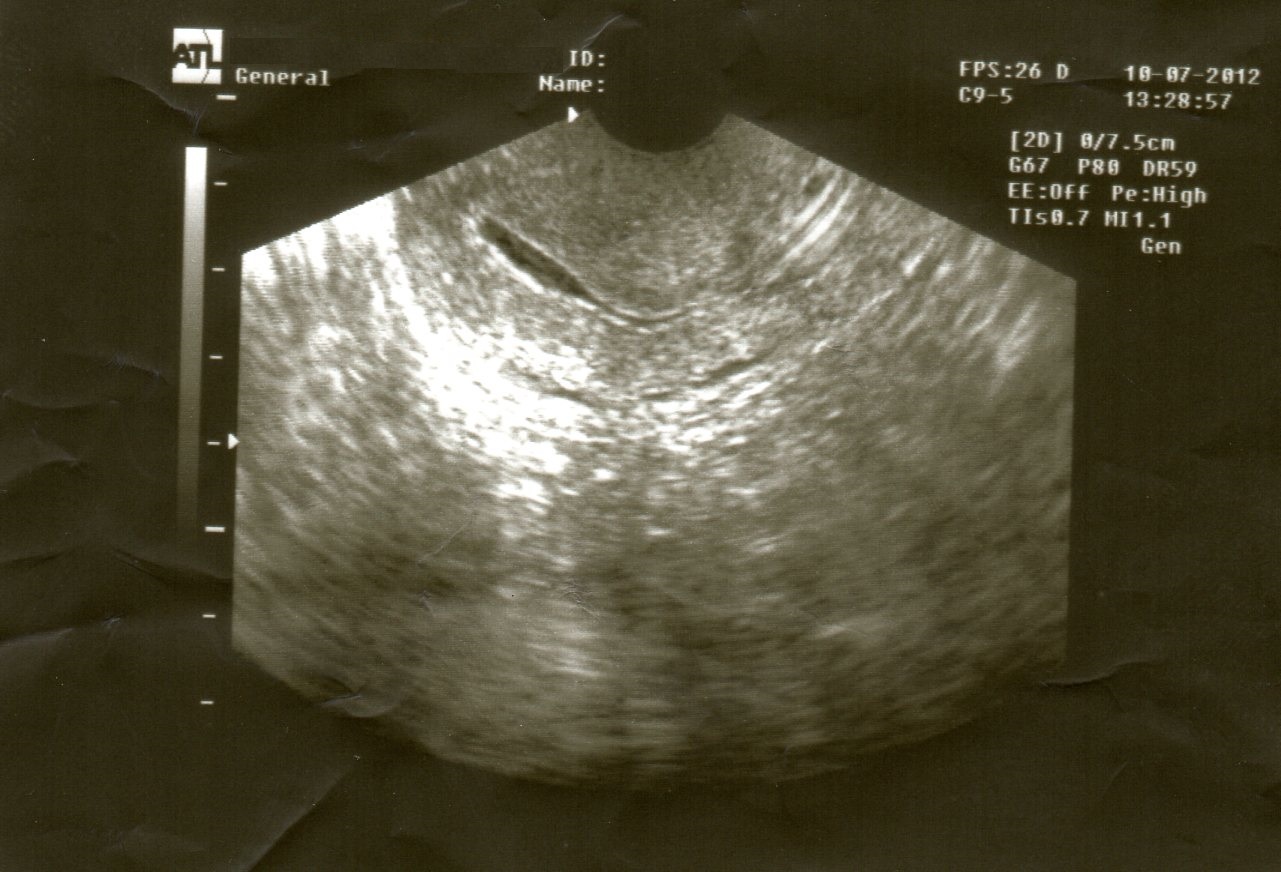

Η υπερηχογραφική απεικόνιση των έσω γεννητικών οργάνων παρέχει χρήσιμες πληροφορίες για τη διάγνωση των περισσοτέρων παθήσεων των έσω γεννητικών οργάνων όπως και για τον έλεγχο της γονιμότητας. Με το γυναικολογικό υπερηχογράφημα μπορούμε να ανιχνεύσουμε:

√ Υπερπλασία ενδομητρίου

√ Πολύποδες ενδομητρίου

√ Ινομυώματα μήτρας

√ Αδενομύωση μήτρας

√ Κακοήθη μορφώματα μήτρας και ωοθηκών

√ Κυστικά μορφώματα ωοθηκών

√ Παρακολούθηση ωορρηξίας σε φυσιολογικό κύκλο και κατόπιν ωοθηκικής διέγερσης

√ Πολυκυστικές ωοθήκες